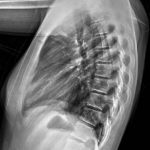

Amplio espectro de estudios

Además del tomógrafo dental, que realiza panorámicas dentales y tomografías, y permite realizar laminografías de la articulación temporomandibular (ATM) y placas de macizo facial para casos como fracturas, el servicio también ofrece estudios especializados como espinogramas y mediciones de miembro inferior con el equipo Pimax. Estos estudios de alta calidad son muy requeridos por traumatólogos de la ciudad y zonas aledañas. La calidad de imagen es tal que, según el Lic. Quiroga, pacientes de ciudades vecinas viajan a Mercedes para ser atendidos.